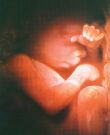

19 haftalık gebelik

Bebeğinizin cildi lanugo adı verilen ipeksi tüylerle kaplı. Bu haftadan itibaren vernix caseosa (verniks kazeoza okunur) adlı madde de üretilmeye başlandı. Bu madde beyaz renkli, krem kıvamında ve bebeğinizin cildini kaplayarak koruyan bir maddedir. Bebeğiniz doğduğunda bu maddenin nasıl birşey olduğunu göreceksiniz. Vernix'in amacı bebeğinizin cildini sürekli olarak maruz kaldığı sıvı ortamdan korumaktır. 9 ay boyunca bir su dolu bir küvette kalsanız cildinizin alacağı şekli düşünebiliyormusunuz?

Bebeğiniz bu haftanın bitiminde tam 280 gram!